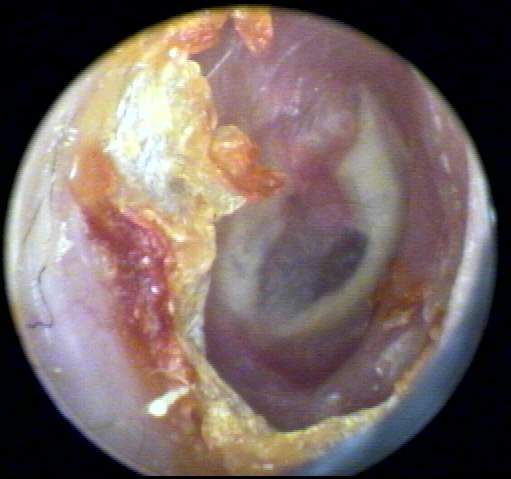

+2: Non-occlusive moderate amount present; likely to interfere with probe tube and ear-insert transducer measurements, hearing aid use, to dimensionally distort or inhibit impression-taking with the possibility of subsequent impaction. Tympanic membrane view may be partially obscured. Removal advised. EXAMPLES:+2/A(25k) | +2/B(23k) | +2/C(21k) | +2/D(21k)